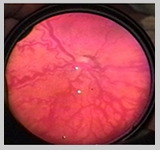

En estos pacientes la dilatación venosa y tortuosidad

vascular o enfermedad Plus suele ser mucho más acentuada.

En ocasiones observamos verdaderos loops arteriovenosos que suelen

regresar una vez que la enfermedad ha sido tratada.

Las hemorragias retinales se ubican no sólo a nivel del

ridge o en el límite entre la retina vascular y avascular,

sino en todo el plano de la retina vascular. Aparecen como verdaderas

petequias sobre esta.